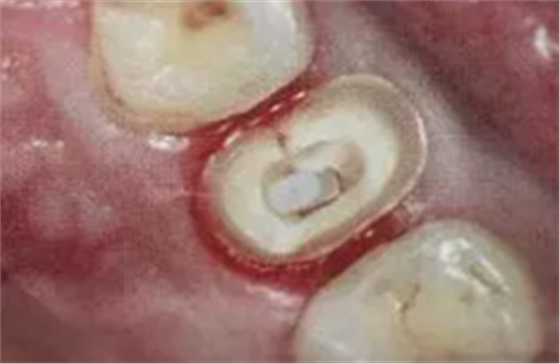

11. 吸取根管內(nèi)多余的粘結(jié)劑

根管內(nèi)涂抹粘接劑時(shí),理想的粘接劑層厚度為25um - 40um,厚度增加或不均勻不利于纖維樁的順暢就位,多余的粘接劑的存在會(huì)加速樹脂水門汀的固化速度。

(粘結(jié)劑涂擦20s,涂抹2-3層)

(紙尖吸出多余粘結(jié)劑)

根管內(nèi)涂抹粘接劑的較規(guī)范操作應(yīng)是:毛刷蘸取粘接劑在根管內(nèi)反復(fù)涂擦20s,涂抹2-3層,然后用紙尖吸取干凈,氣槍吹5s使粘接劑中的溶劑快速揮發(fā)。此操作中,大錐度吸潮紙尖非常關(guān)鍵,它不僅可以吸取多余的粘接劑,同時(shí)也可使粘接劑在根管內(nèi)鋪展均勻。醫(yī)生朋友不要“忽視小物件鑄成大事件。